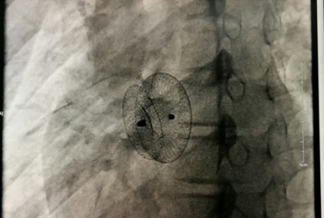

我院成功开展市属医院首例先心病介入封堵术 不用开刀,不会在体表留下疤痕,只需进行局部皮肤麻醉,通过穿刺右侧股静脉插入一根几毫米的导管,将封堵器送至缺损部位释放,先天性心脏病就得到了根治。不久前,15岁的小章在我院成功接受了先天性心脏病介入封堵术,他的心脏结构和功能恢复了正常,学习和生活也得到了恢复。...